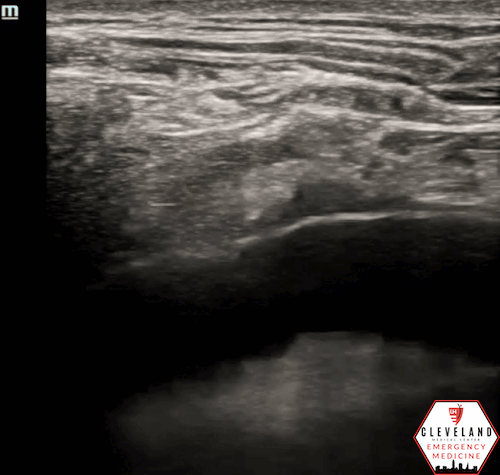

Figure 2. Parasternal approach - Source: NUEM Blog — Pericardiocentesis (nuemblog.com)

Parasternal Approach

• Probe Placement: Left parasternal region, usually 4th intercostal space.

• Probe Orientation: Indicator toward the patient's left shoulder.

• Needle: Insert in-plane at ~45°, directed toward the effusion.

• Pros/Cons: Often preferred due to closer proximity of effusion to the chest wall and distance from lung/liver. The needle trajectory aligns well with cardiac structures, improving needle visualization [4-5].